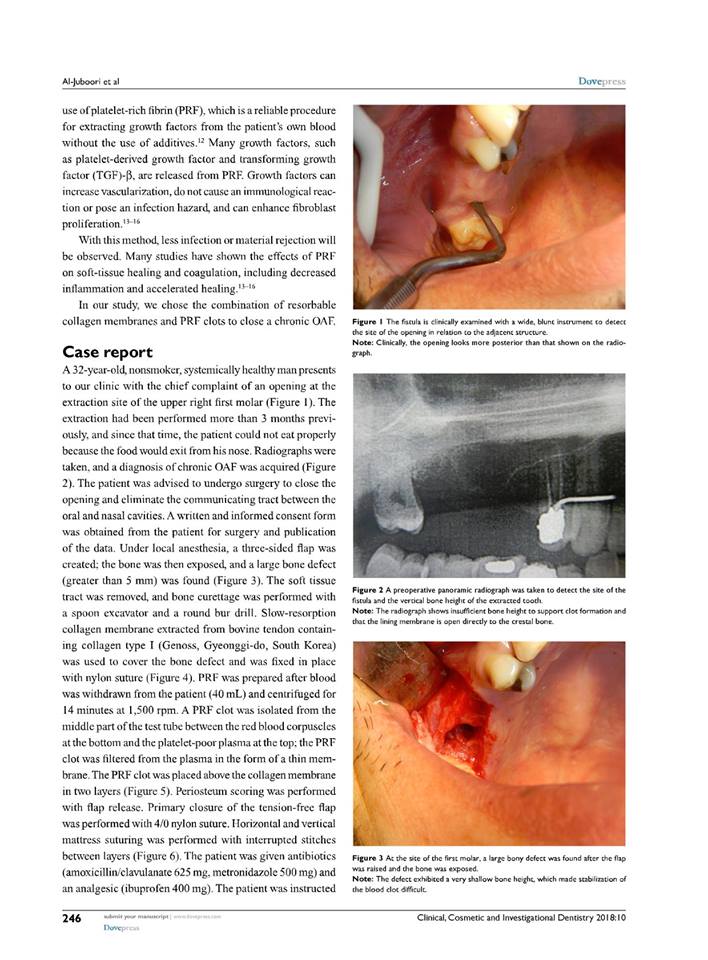

في خطوة علمية جديدة تم نشر بحث من قبل التدريسي د.محمد جاسم محمد في قسم طب الاسنان/امراض اللثة في مجلة

Journal of clinical Cosmetic and investigational dentistry والتي تملك معامل تأثير